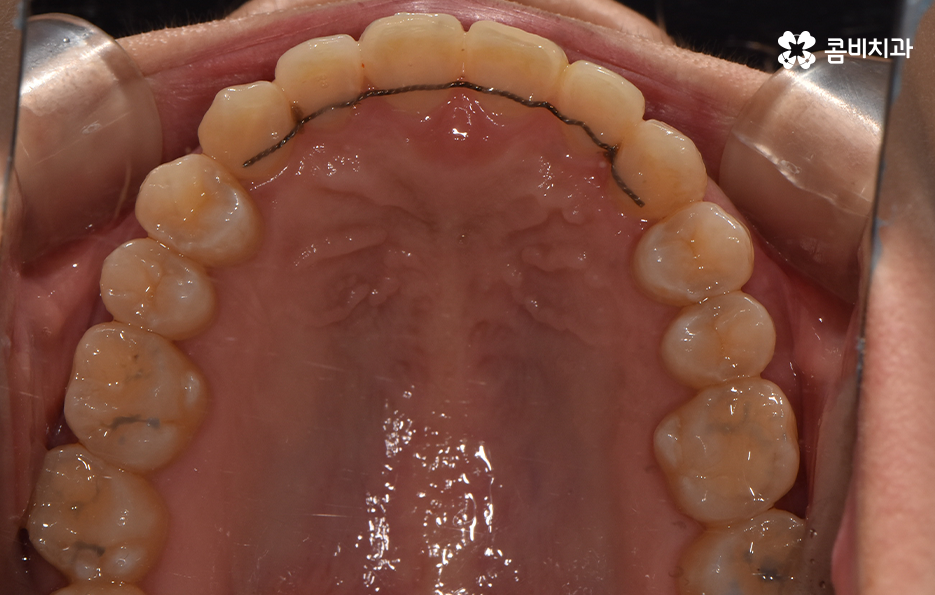

교정 치료는 크게 발치와 비발치치아교정으로 나뉠 수 있는데 비발치치아교정의 경우에는 아무래도 치아가 움직이는 양도 적고 그에 따라 교정 기간도 짧은 편에 해당되고 있어요.

교정을 하게 되면 아무래도 치아와 잇몸이 함께 움직이기 때문에 어느정도는 잇몸이 약해질 가능성이 있는데 비발치치아교정의 경우에는 치아의 이동이 큰 편은 아니기 때문에 발치교정에 비해서는 잇몸이 약해지는 정도 및 확률이 줄어들 수 있어요

반면에 발치교정의 경우에는 최소 1년 6개월 ~ 2년 이상의 교정 기간이 소요되며 치아가 빠진 공간에 나머지 치아들이 메우면서 치아의 이동이 비발치치아교정에 비해 많기 때문에 그에 따라 치아는 물론 치조골의 이동도 감안해야 하므로 치료 기간도 더 오래 걸리고 잇몸도 좀더 약해질 수 있는 확률이 발치교정에 비해서는 높은 편으로 볼 수 있는데요.

이러한 비교는 기본적으로 치아 이동의 정도 차이로 인해 치아 뿐 아니라 치조골의 이동이 큰 만큼 확률적으로 잇몸이 약해질 가능성이 상대적으로 크다는 의미로 볼 수 있어요.

그렇기 때문에 비발치치아교정이 좋다고 생각하기 보다는 개인에 따라서는 치아의 이동 공간 확보를 충분히 하기 위해 발치가 필요한 경우도 있고 얼굴 변화나 부정교합의 개선을 위해 발치가 필수적인 경우도 있을 거예요

반면에 비발치치아교정으로도 충분히 좋은 결과를 얻을 수 있는 경우도 있을텐데 이러한 치료 과정 상의 특징과 장단점을 고려하여 자신의 치료 계획을 경험 많고 숙련된 교정 전문의와 잘 상의하실 필요가 있어요